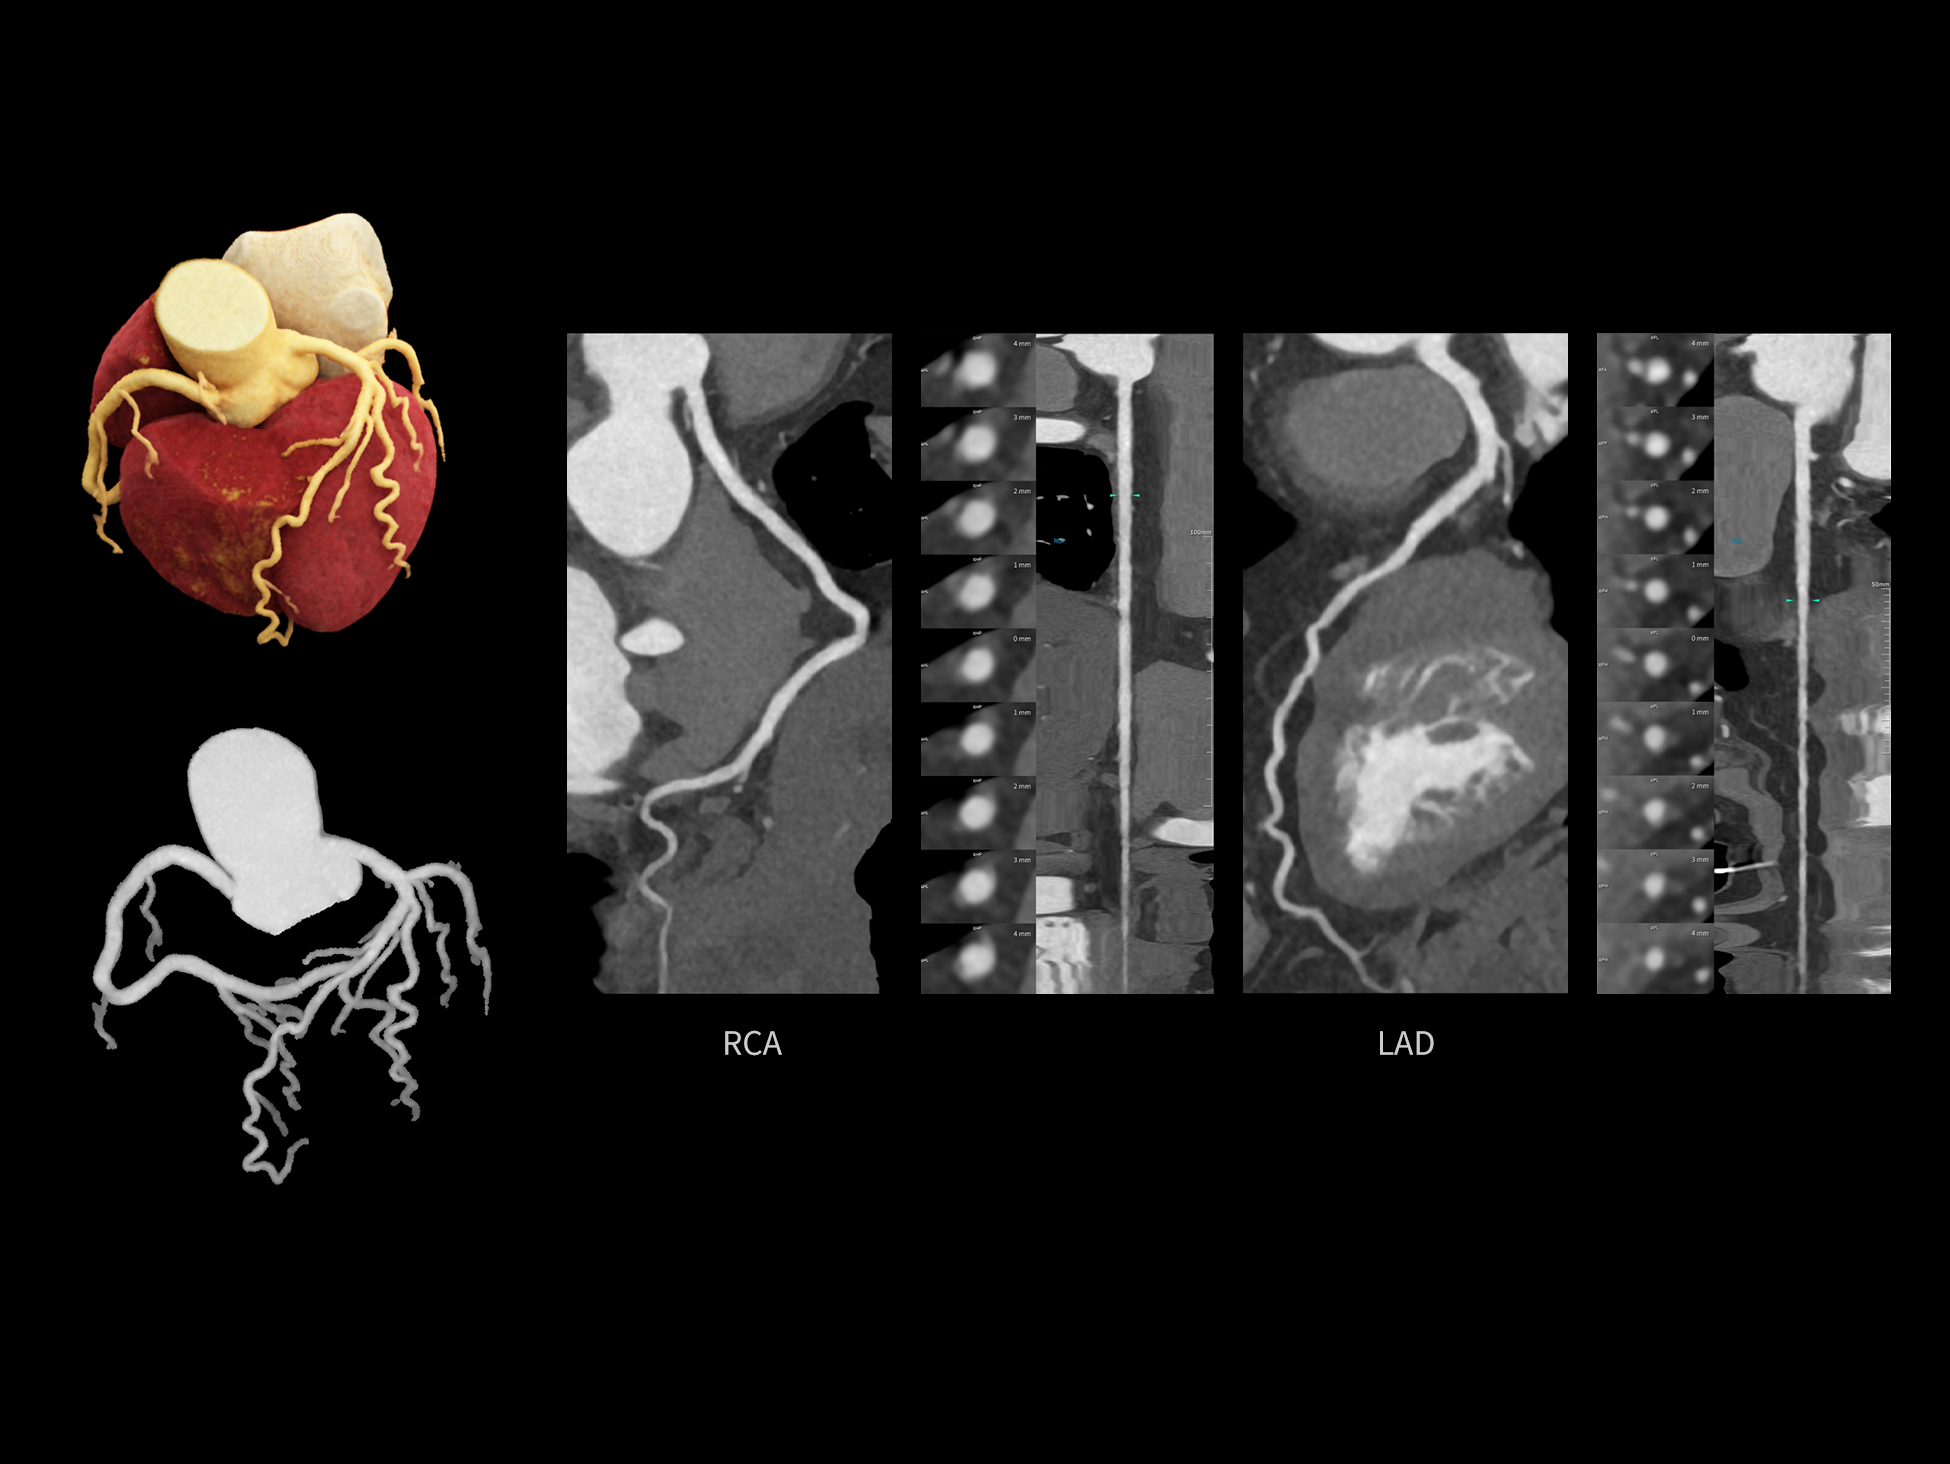

全时心脏

uCT SiriuX® 挑战心脏成像时间分辨率的极限,精准捕捉心脏全周期的动态变化。无论静态解剖形态,还是动态功能表现,都能清晰呈现,让心脏不再是“定格”的器官,而成为可视的生命律动。

CardioCapture 2.0 通过“识别–追踪–建模–校正”的完整流程,精准分割心脏结构,动态追踪运动轨迹,并构建多时相运动场,最终实现冠脉、瓣膜、心肌及心室结构的同步校正,清晰洞见每一次心跳细微变化,真正将心脏动态掌握于毫秒之间。

CardioCapture 2.0 在目标时相前后重建多时相影像,通过深度学习网络精准提取冠脉中心线,进而建立时相间运动模型,实现对冠脉分段图像的精准运动校正。

CardioCapture 2.0 可对心肌、瓣膜及心室等结构进行同步运动校正。基于深度学习的心脏精细分割,实现了更完整的心脏全局信息提取,能有效抑制全心运动伪影,显著提升心脏细节的清晰度与诊断可靠性。

冠脉运动校正

全心结构运动校正

心脏成像,自由掌控